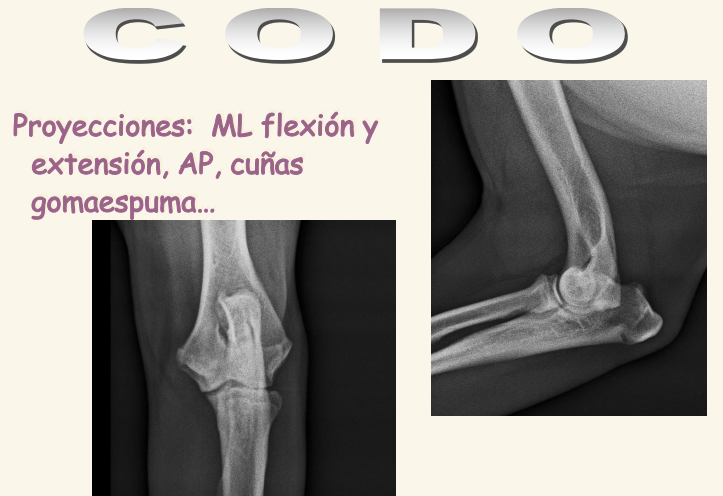

Codo

El condilo medial es mas fuerte que el lateral. Se dan fracciones en T o en Y. Luxacicones son mas dificiles que en codo

Existe la displasia del codo

- FCM: Fragmentación del Coronoides Medial, una de las lesiones típicas de displasia de codo

- NUPA: No Unión del Proceso Anconeo

- OCD: Osteocondritis disecante del condilo medial

- Incongruencia, mala articulacion de los 3 huesos.

- Se suele ver esclerosis subcondral que es la presencia de distinta densidad en el hueso bajo la articulación